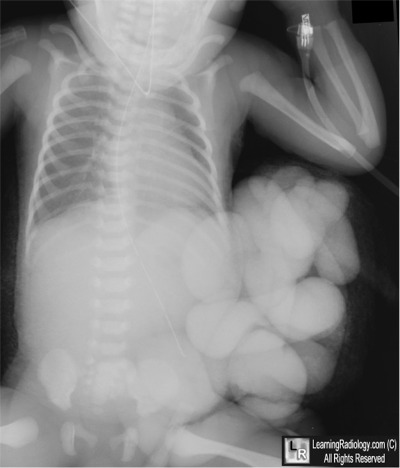

- Newborn with obvious abdominal wall defect

3. Gastroschisis

Gastroschisis

- Herniation of abdominal contents through a small (2-5 cm) defect in the abdominal wall, usually just to the right of the umbilicus

- Usually involves small bowel

- Herniation of other visceral organs is rare

- No surrounding membrane

- There are usually no associated congenital defects